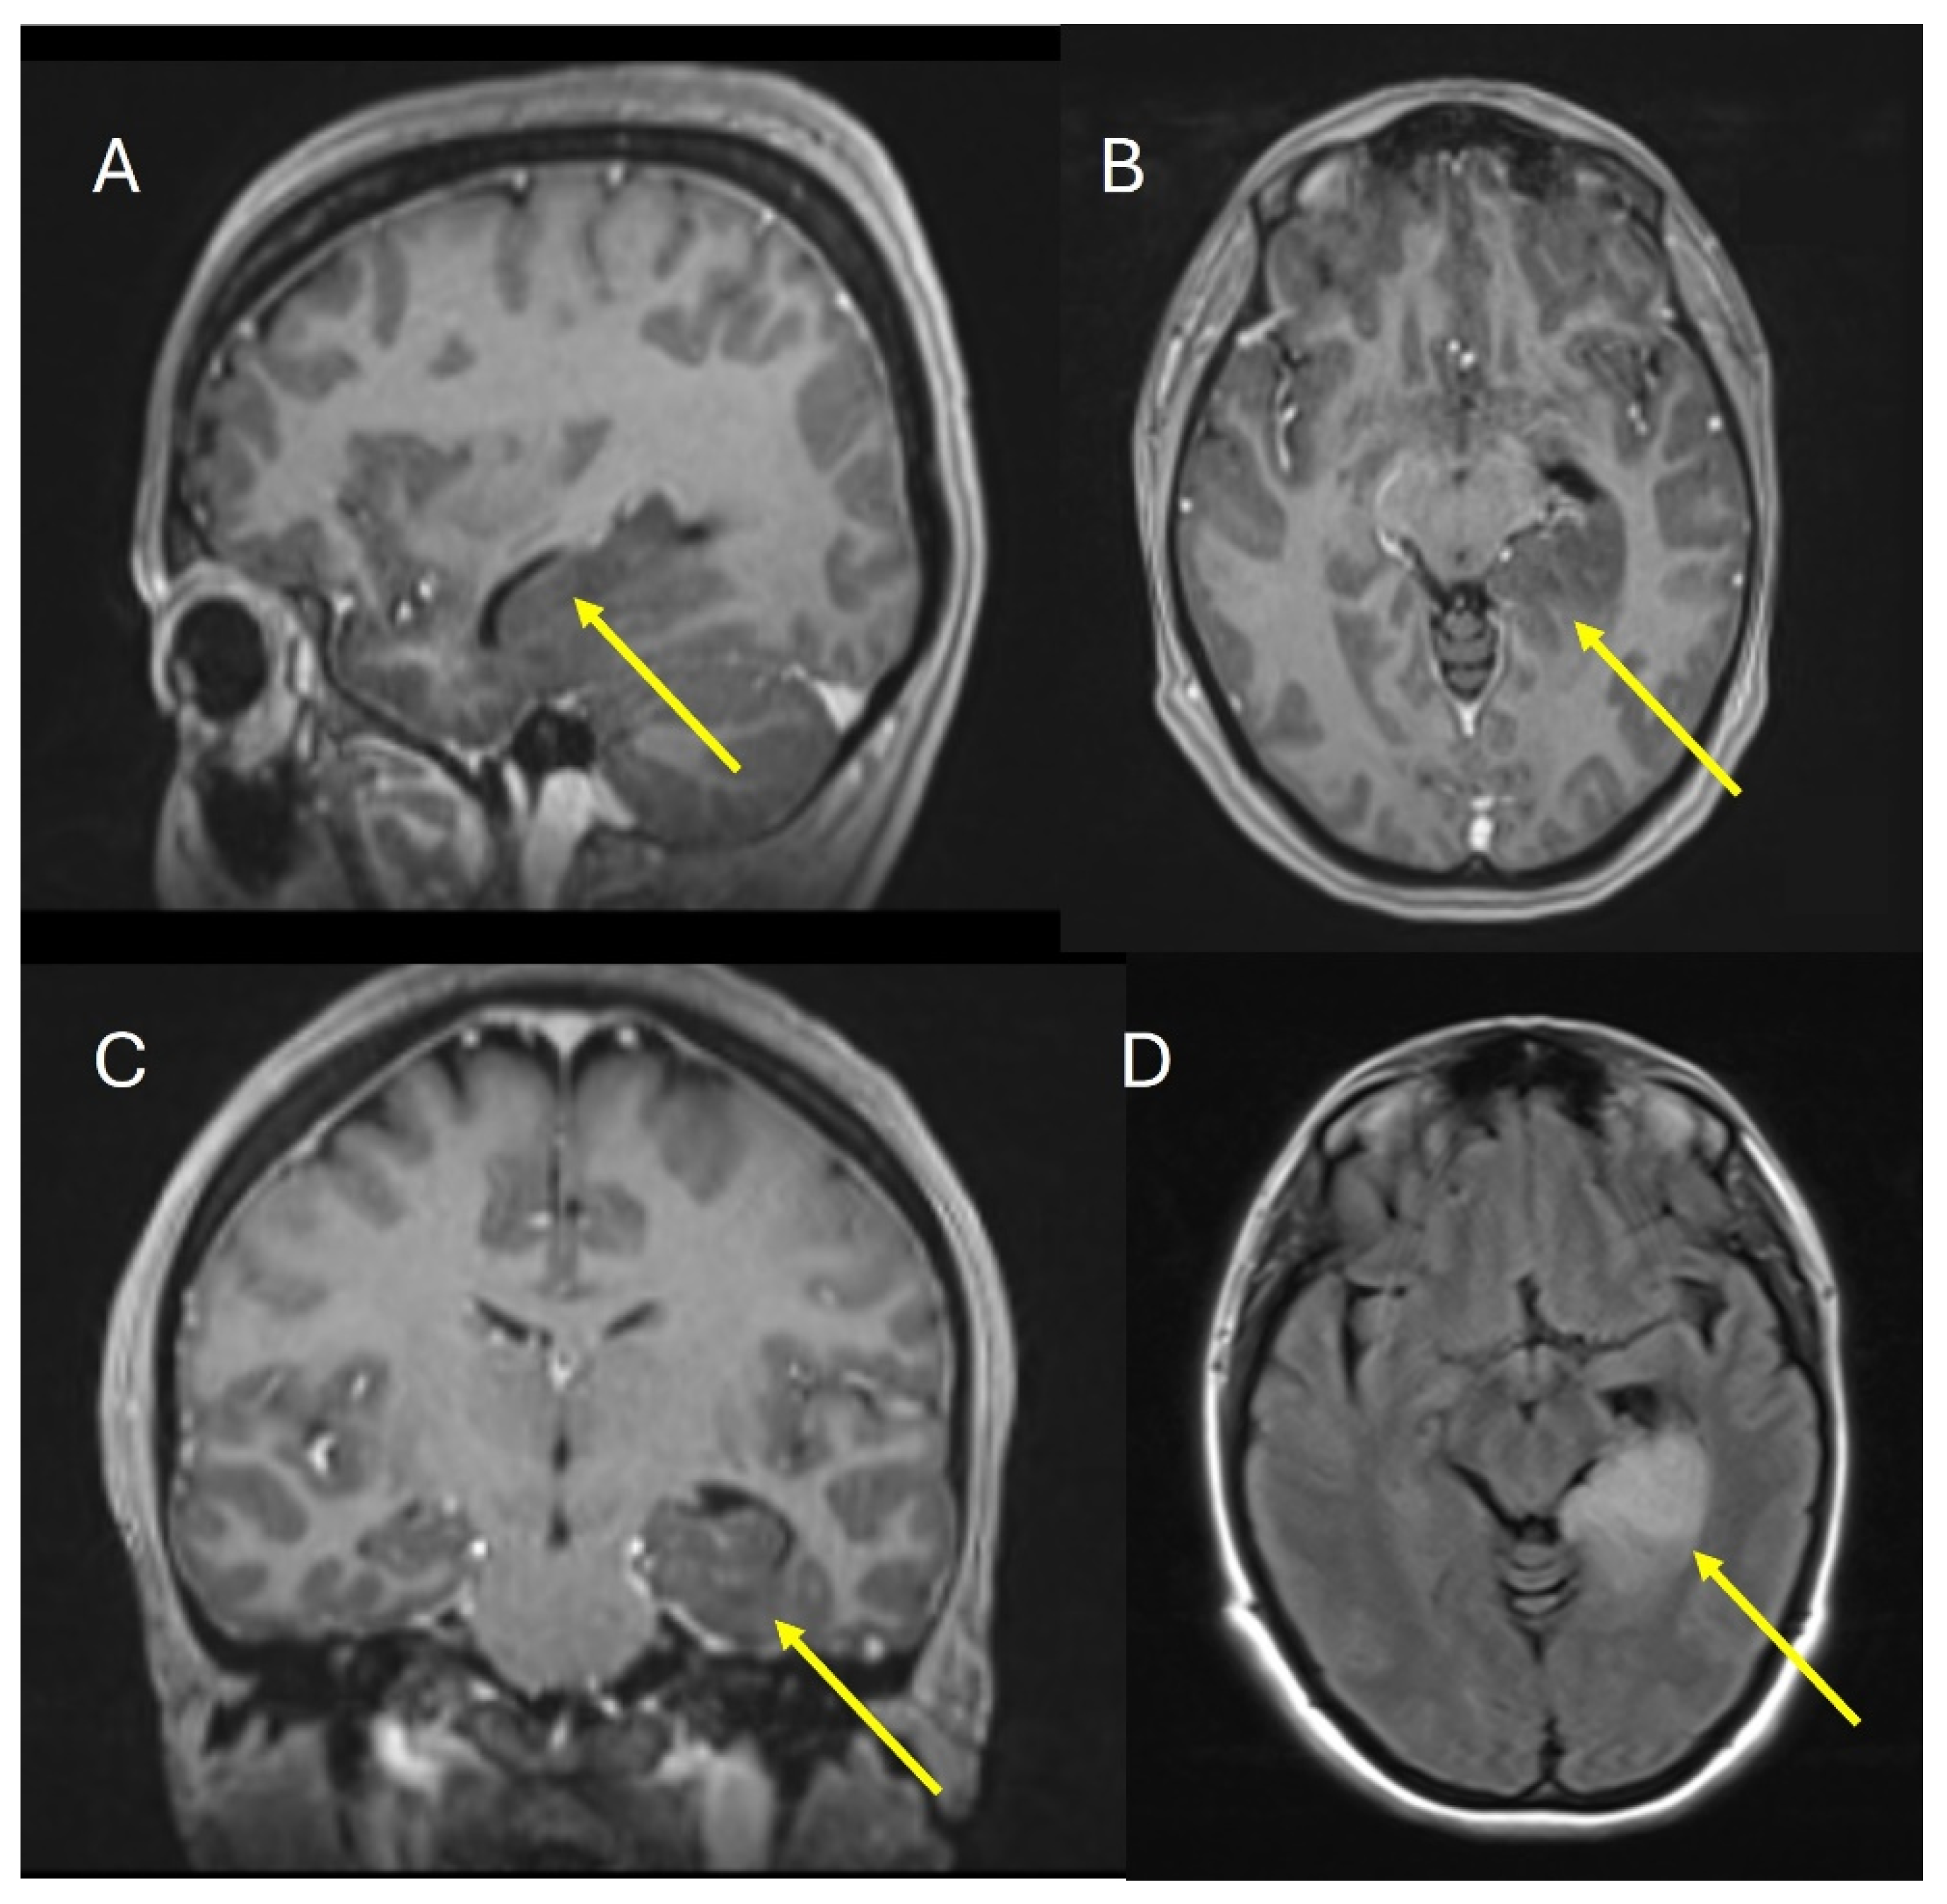

The patient underwent an MRI of the brain with contrast, which revealed a lesion occupying the left hippocampal formation and the parahippocampal gyrus. The lesion was not contrast enhanced; it was hypo-intensive in T1WI and high-intensive in FLAIR and T2WI (Figure 2). The patient was offered and underwent a biopsy of the lesion.

Figure 2.

MRI of the brain. (A) Saggital image T1WI, (B) Axial image T1WI, (C) Coronal image T1WI, (D) FLAIR axial image. The yellow arrow shows the hippocampal formation and parahippocampal gyrus.